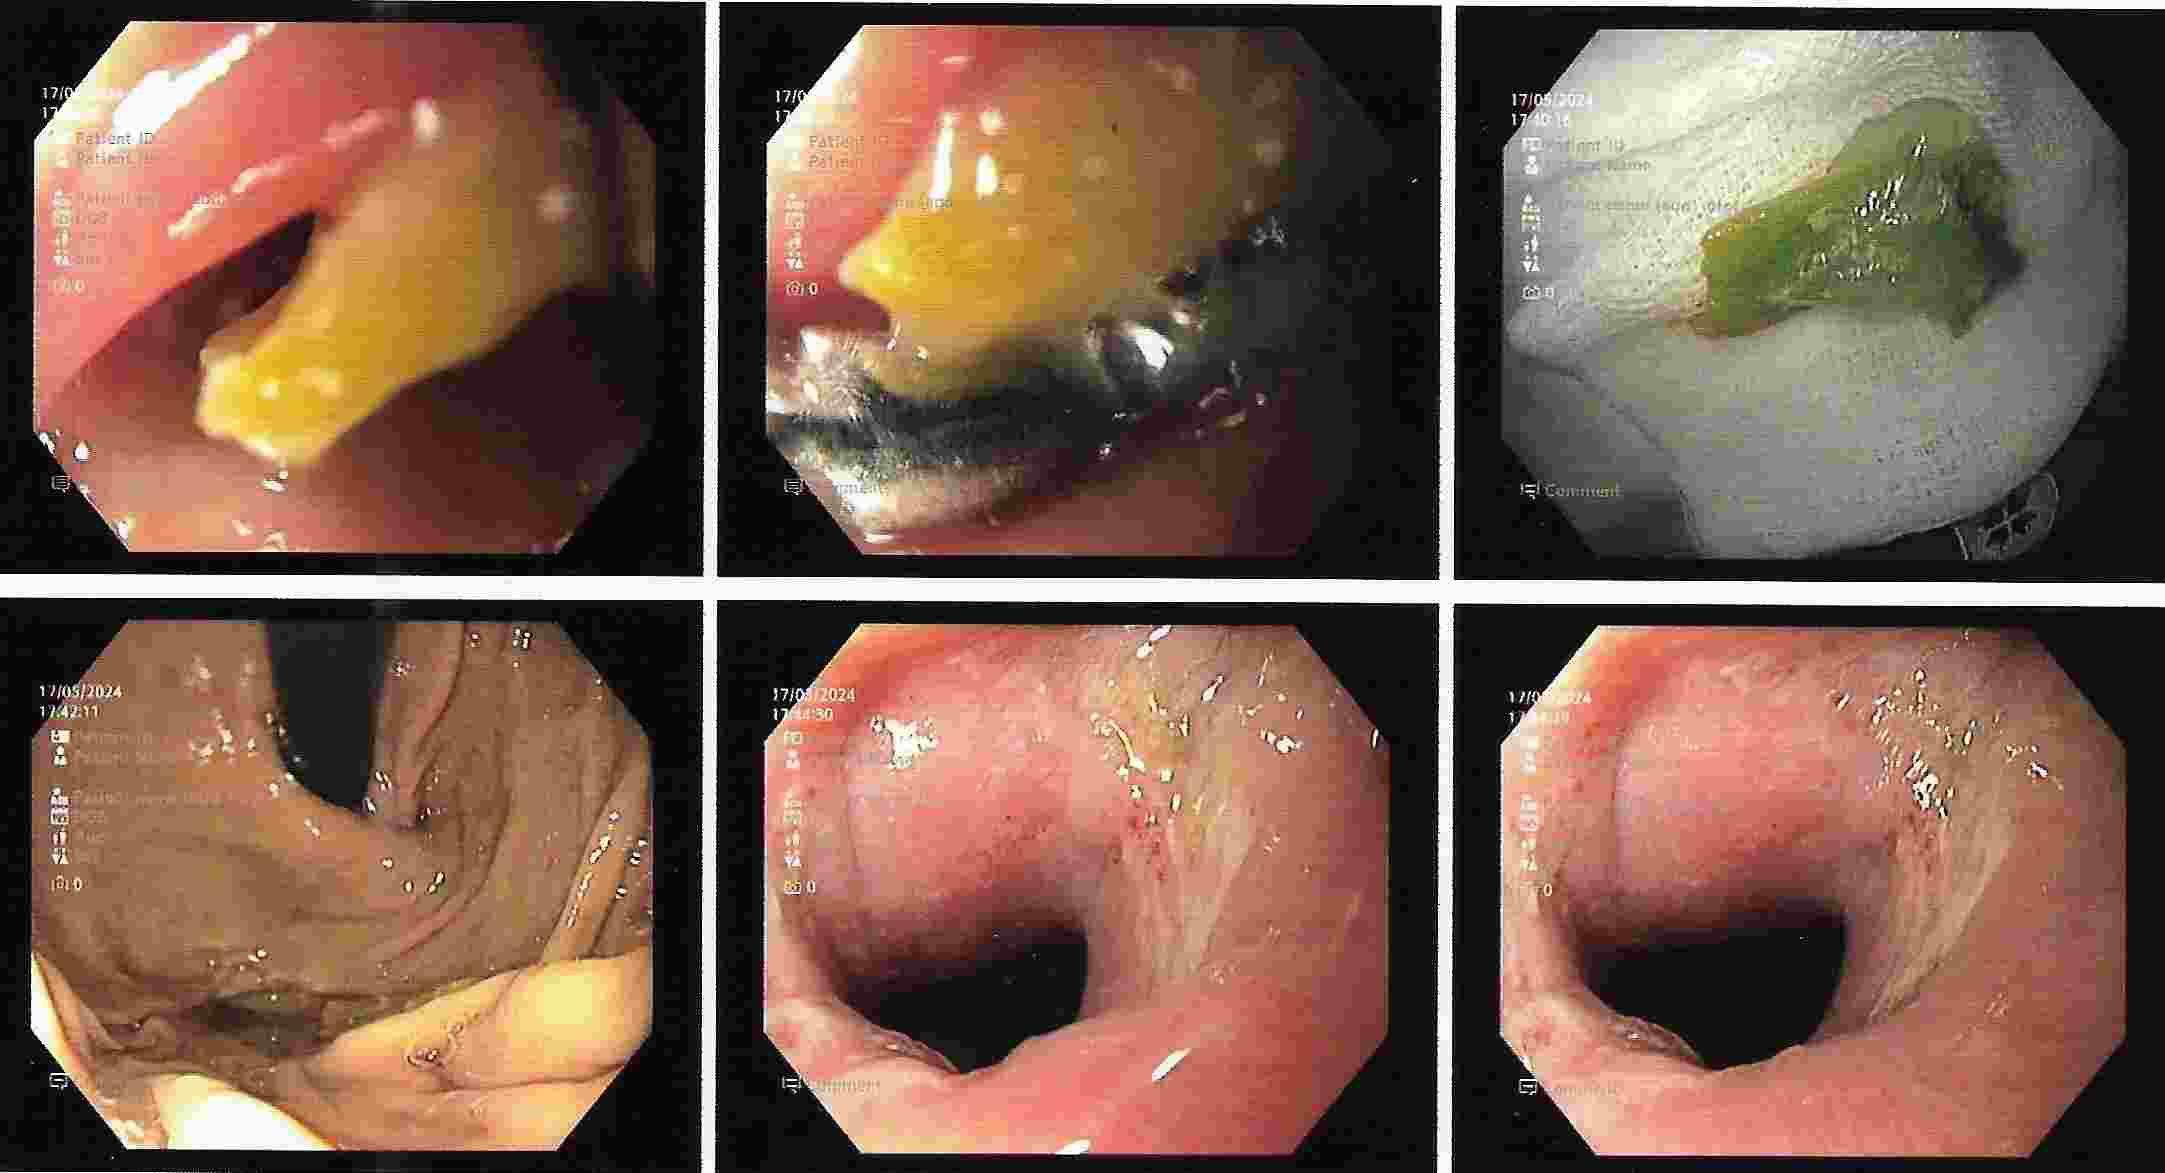

A. UPPER GI ENDOSCOPY popularly known as GASTROSCOPY.

This is done commonly as an out patient procedure with mild sedation without anaesthesia.

Patient can resume with daily routine within an hour.

But should not drive for 2 hours if patient has received sedation.

This procedure allows diagnosis of diseases of upper Gastrointestinal tract, esophagus, stomach and duodenum.

UPPER GI ENDOSCOPY

Common conditions for which this procedure is advocated are as follows :